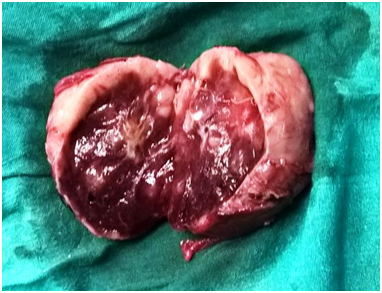

Paragangliomas can develop anywhere along the midline of the retroperitoneum. The exact incidence of retroperitoneal paragangliomas is unknown, although males are typically affected more frequently than Females. In addition, most patients are diagnosed between 30 and 45years of age.1 Clinically, patients with a retroperitoneal paraganglioma often present with back pain or a palpable mass.2 Conventional treatment for paragangliomas typically involves complete surgical excision, while surgical debulking is considered a mainstay of palliative therapy for malignant paragangliomas. In some cases, complete excision is difficult due to the highly vascular nature of paragangliomas and their proximity to major blood vessels (Figure 1-4).

Figure 4 Cut section of the tumor.